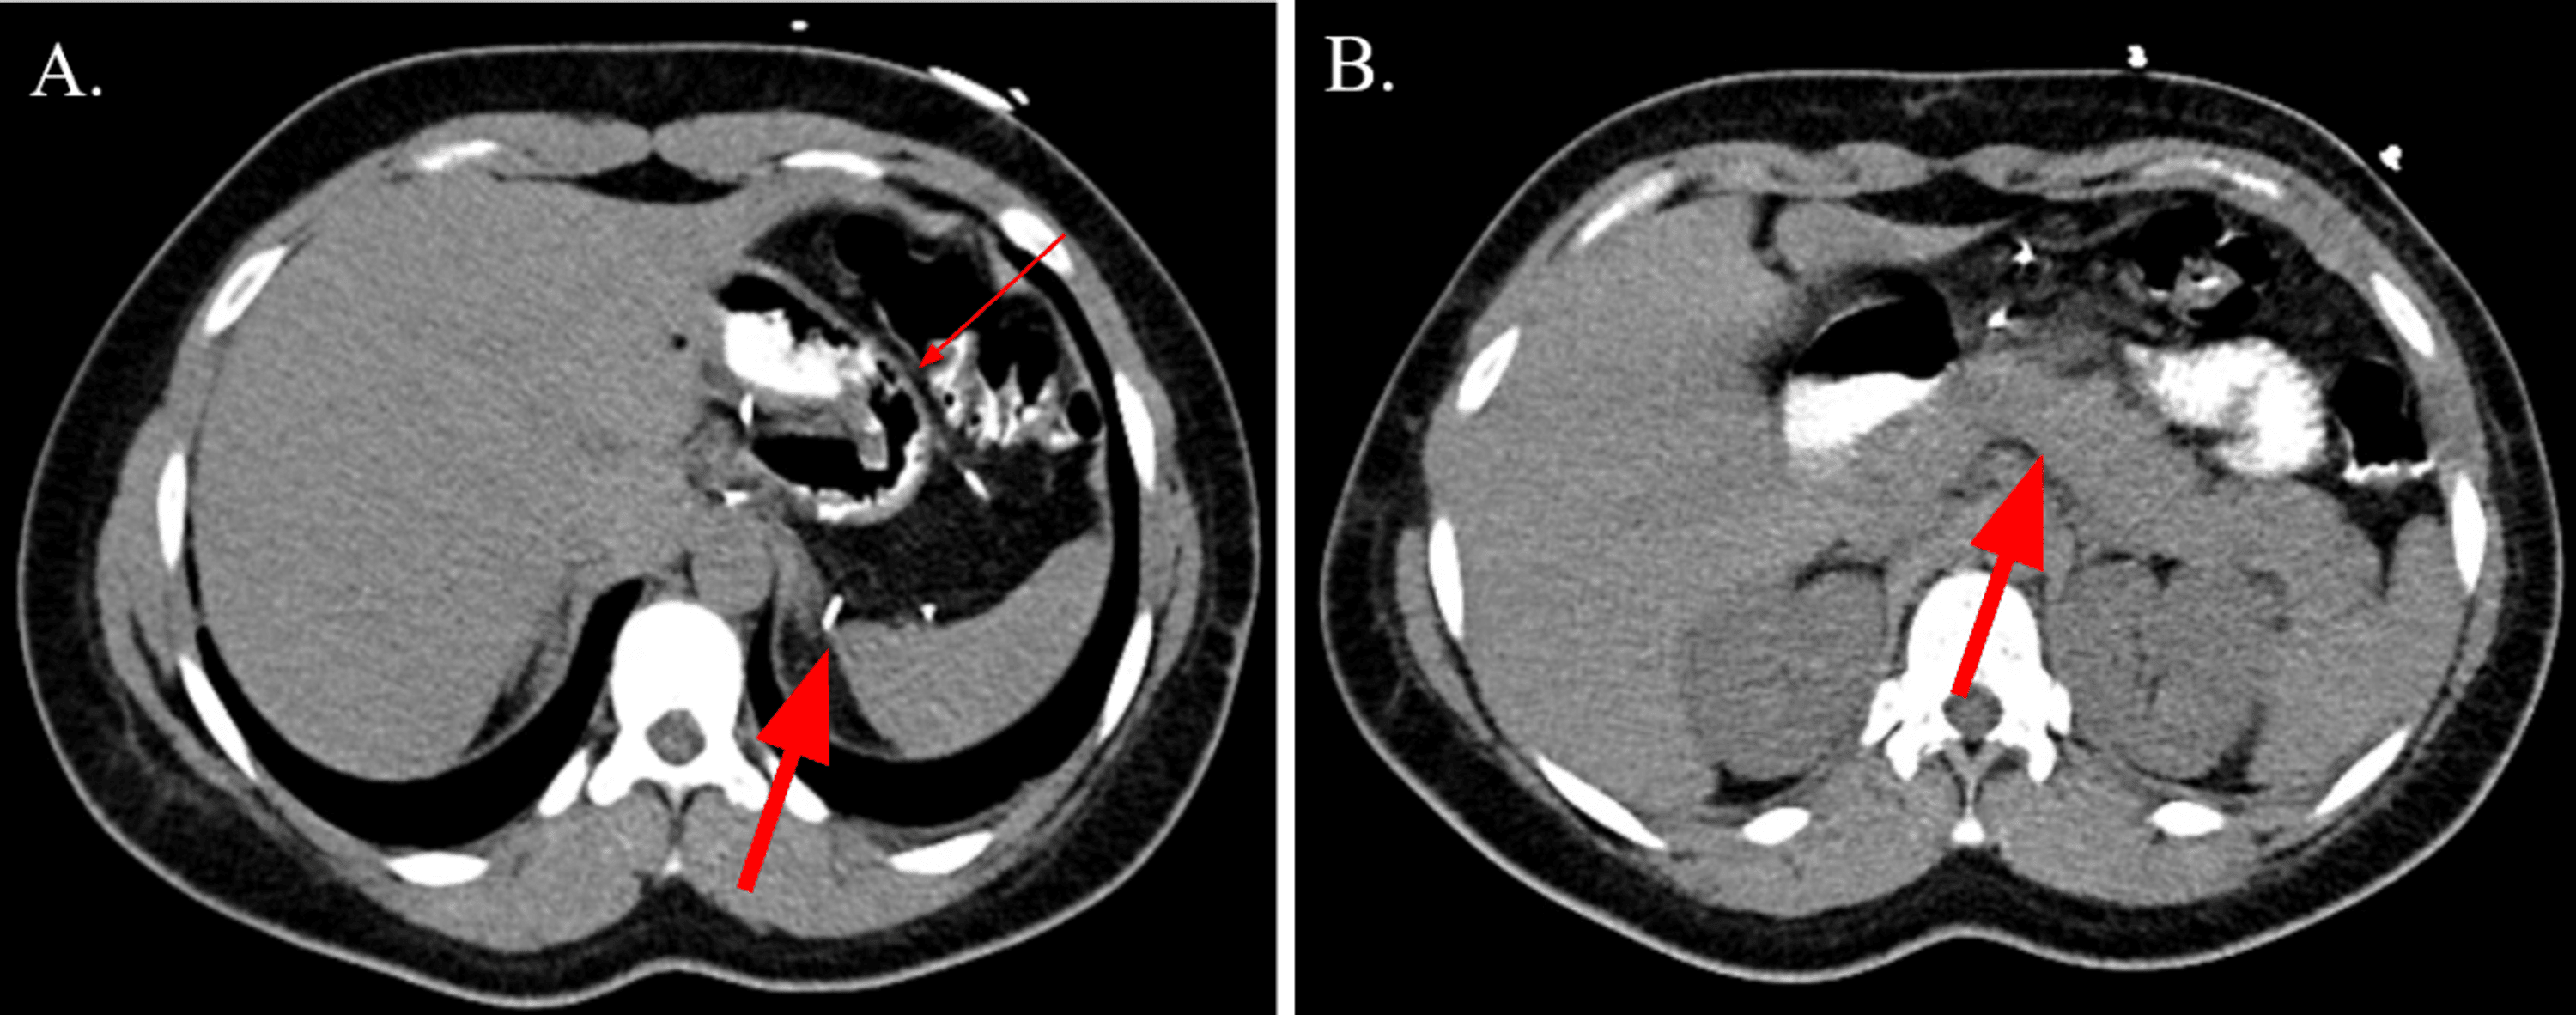

Figure 1 from Delayed Presentation of Gastric Volvulus with Gastric Outlet Obstruction after Gastric Volvulus Post Sleeve Gastrectomy Gastric volvulus after sleeve gastrectomy is a rare entity presenting vague symptoms and signs and requires a high index of suspicion from the. After undergoing gastric sleeve surgery, it is important to be aware of the risk factors and potential causes that can lead to a twisted stomach, also known as gastric volvulus. It is crucial to recognize both common. Gastric Volvulus Post Sleeve Gastrectomy.

Figure 25 from Imaging of bariatric surgery normal anatomy and postoperative complications Gastric Volvulus Post Sleeve Gastrectomy Gastric volvulus is characterized by rotation of the stomach along its long or short axis leading to variable degrees of gastric outlet. Gastric volvulus after sleeve gastrectomy is a rare entity presenting vague symptoms and signs and requires a high index of suspicion from the. After undergoing gastric sleeve surgery, it is important to be aware of the risk factors. Gastric Volvulus Post Sleeve Gastrectomy.

Figure 1 from Intrathoracic sleeve gastrectomy migration with gastric volvulus treated with Gastric Volvulus Post Sleeve Gastrectomy Gastric volvulus after sleeve gastrectomy is a rare entity presenting vague symptoms and signs and requires a high index of suspicion from the. We are reporting a case of gastric volvulus post laparoscopic sleeve gastrectomy, which was managed conservatively. After undergoing gastric sleeve surgery, it is important to be aware of the risk factors and potential causes that can lead. Gastric Volvulus Post Sleeve Gastrectomy.

(PDF) Intrathoracic sleeve gastrectomy migration with gastric volvulus treated with laparoscopic Gastric Volvulus Post Sleeve Gastrectomy It is crucial to recognize both common and unusual complications of sleeve gastrectomy to properly diagnose and manage. After undergoing gastric sleeve surgery, it is important to be aware of the risk factors and potential causes that can lead to a twisted stomach, also known as gastric volvulus. Gastric volvulus after sleeve gastrectomy is a rare entity presenting vague symptoms. Gastric Volvulus Post Sleeve Gastrectomy.